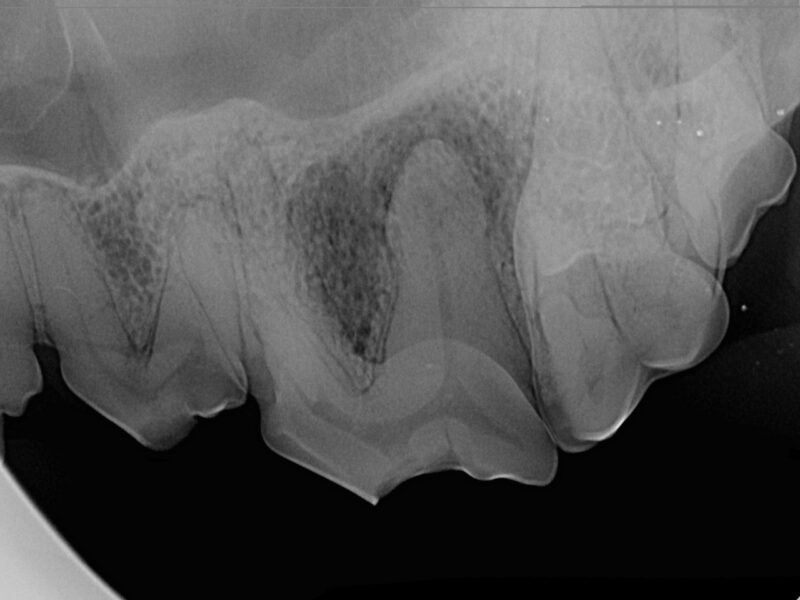

Sechs Monate nach der Versiegelung wird Mia nochmals in der Klinik vorgestellt, um den versiegelten Zahn in Narkose zu röntgen. Auch wenn zum Zeitpunkt der Versiegelung keine Anzeichen für eine Infektion des Wurzelkanals bestand, kann nicht ausgeschlossen werden, dass bereits Bakterien eingedrungen waren. Sollte das der Fall sein müsste man sechs Monate später Anzeichen für eine Infektion auf den Röntgenbildern sehen.

Mia hat Glück gehabt - alles sieht so aus wie es soll, und sie kann ihren Reißzahn behalten. Die Besitzerin achtet ab jetzt darauf, Mia nichts kauen zu lassen, was ihren Zähnen schaden könnte. Hierbei gilt: alles, was nicht mit dem Fingernagel eingedrückt werden kann, ist zu hart.